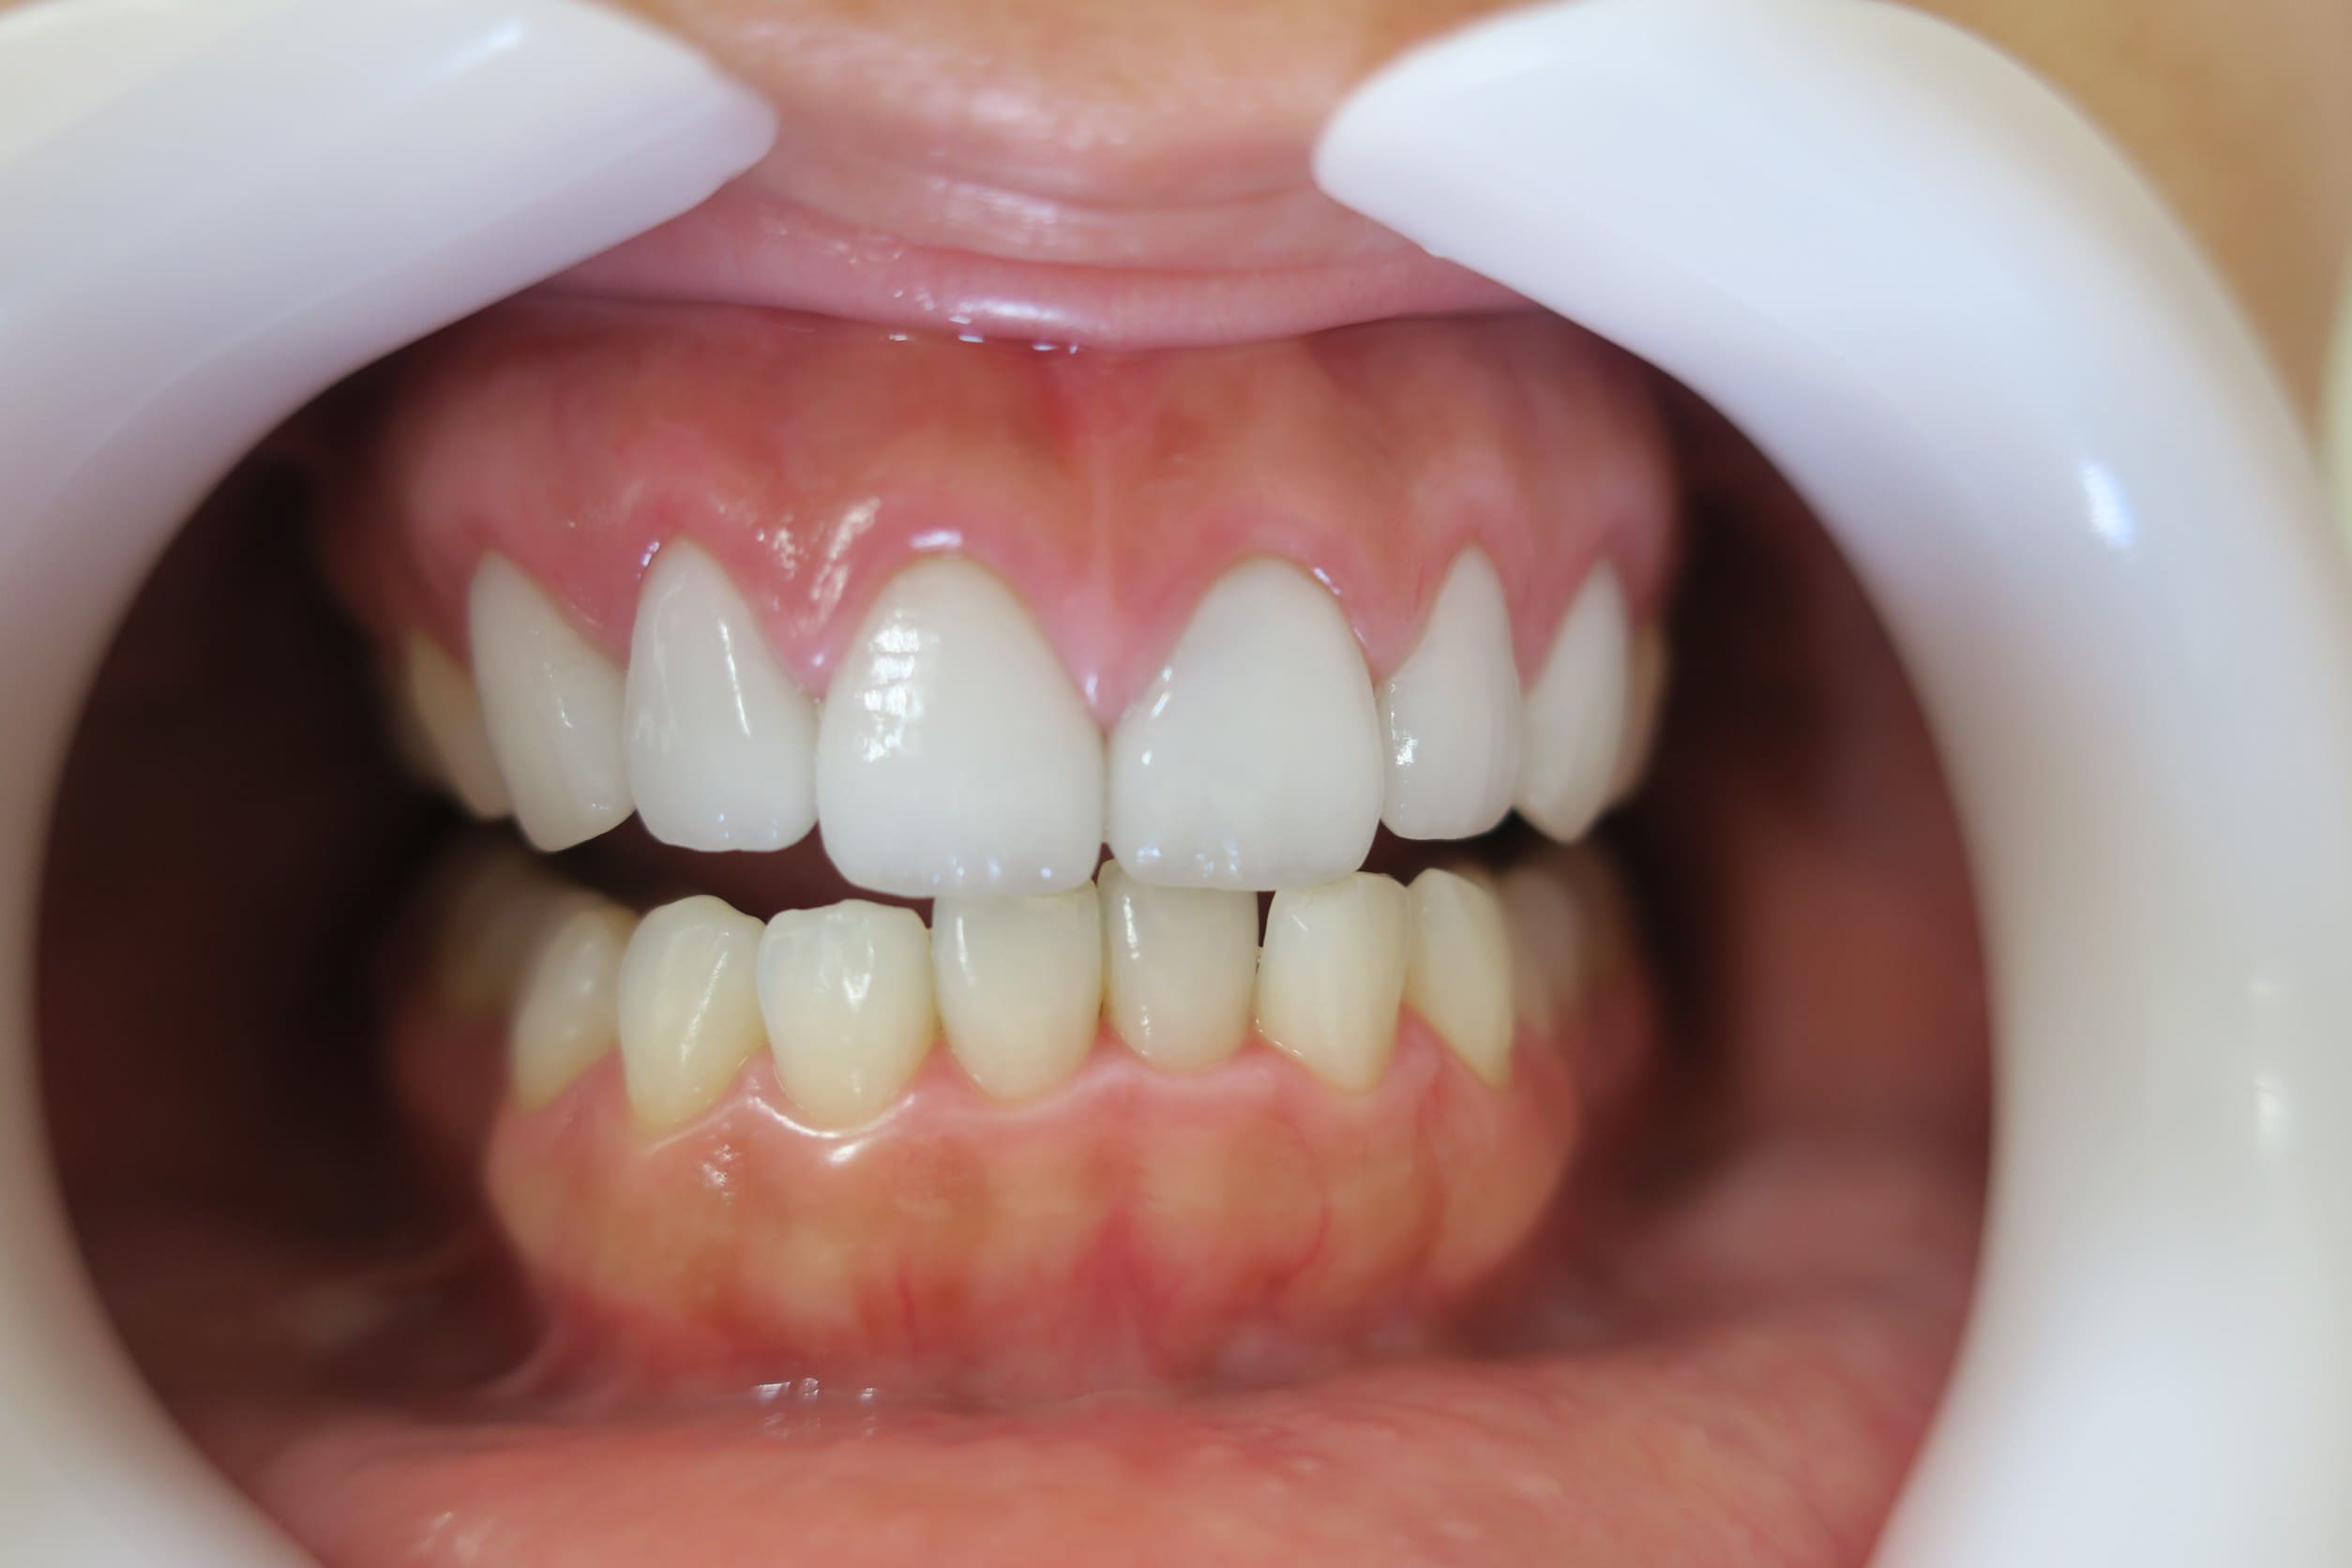

● 歯根が折れ保存不可の歯を抜歯して、そのスペースに八重歯を並べた症例

藤沢デンタルオフィスの虫歯や破折で抜歯後の部分矯正